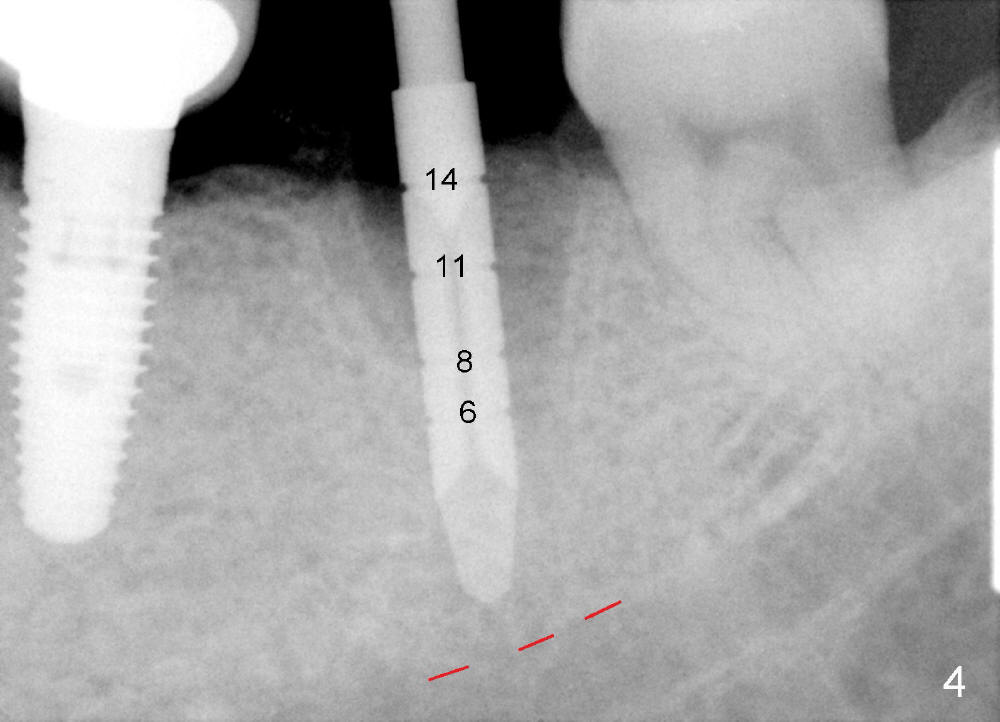

The septum of the socket is thin (Fig.3*), and easily removed, leaving a large socket. Osteotomy is initiated with 2 mm pilot drill in the middle of the socket, slightly mesiolingual, since the buccal and distal bone is low and defective. Reamers (2.5 to 4 mm in diameter) are sequentially used to enlarge osteotomy and harvest autogenous bone (Fig.4 (3 mm reamer in place). When 5 mm tap is placed, there is no stability. Six mm tap gains some stability, but the socket is not closed. Seven mm tap achieves strong stability and is closing the socket (Fig.5). Ultimately a 7x14 mm implant is placed with insertion torque more than 60 Ncm (Fig.6). The implant almost obliterates the socket (Fig.7). The harvested autogenous bone is placed in the buccal and distal aspects of the socket before Chromic gut suture (4-0) is placed distally. Fig.8,9 show the healing socket 6 days and 1.5 months postop, respectively. Osteointegration appears to occur in 2.5 months (Fig.10, compare to Fig.6). Bone level remains the same 1 year post cementation (Fig.11).